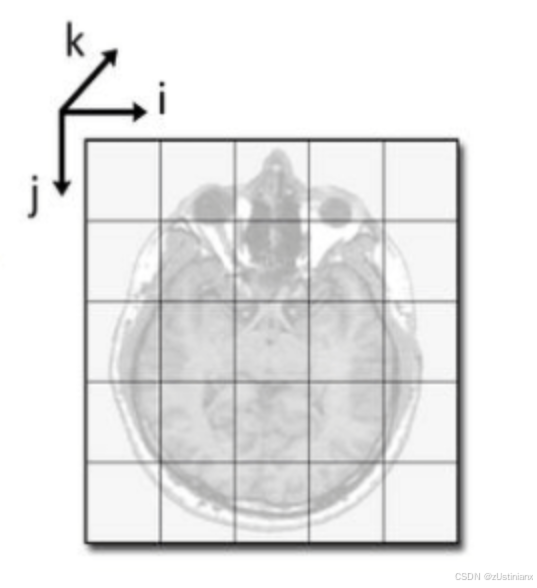

病人坐标系与数组坐标系

病人坐标系以毫米为单位,而数组坐标系以体素为单位。

需要将病人坐标系中的结节中心坐标转换为数组坐标(I, R, C),以便从 CT 数据中提取感兴趣区域。

坐标转换

从病人坐标系到数组坐标系:通过方向矩阵、体素大小和原点偏移量进行转换。

从数组坐标系到病人坐标系:执行逆操作。

实现了xyz2irc()和irc2xyz()函数,用于完成这两种转换。